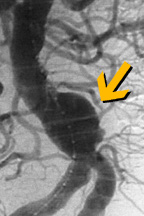

تمدد الأوعية الدموية يمكن أَنْ يكتشف بالفحص، بإستخدام صور الأشعة السينية للصدر أو للمعدة ، أَو بإستعمال التصوير بإستخدام النظائر المشعة أو الموجات فوق السمعية. يمكن أيضا أستعمال تصوير الرنين المغناطيسي، أو سي تي سكان tomographycomputed tomography (CT) scanning.

الإجراء يتضمن إستعمال قسطرة لإدخال أداة تسمى وصلة حلقة فاتحة Stent Graft. الحلقة الفاتحة توضع داخل الشريان في موقع التمدد. يجرى الدم خلال الحلقة الفاتحة، مما يؤدي إلى خفض الضغط على جدار الشريان الضعيف. هذا الإنخفاض في الضغط يمكنه أن يمنع التمدد من تفجير الشريان.